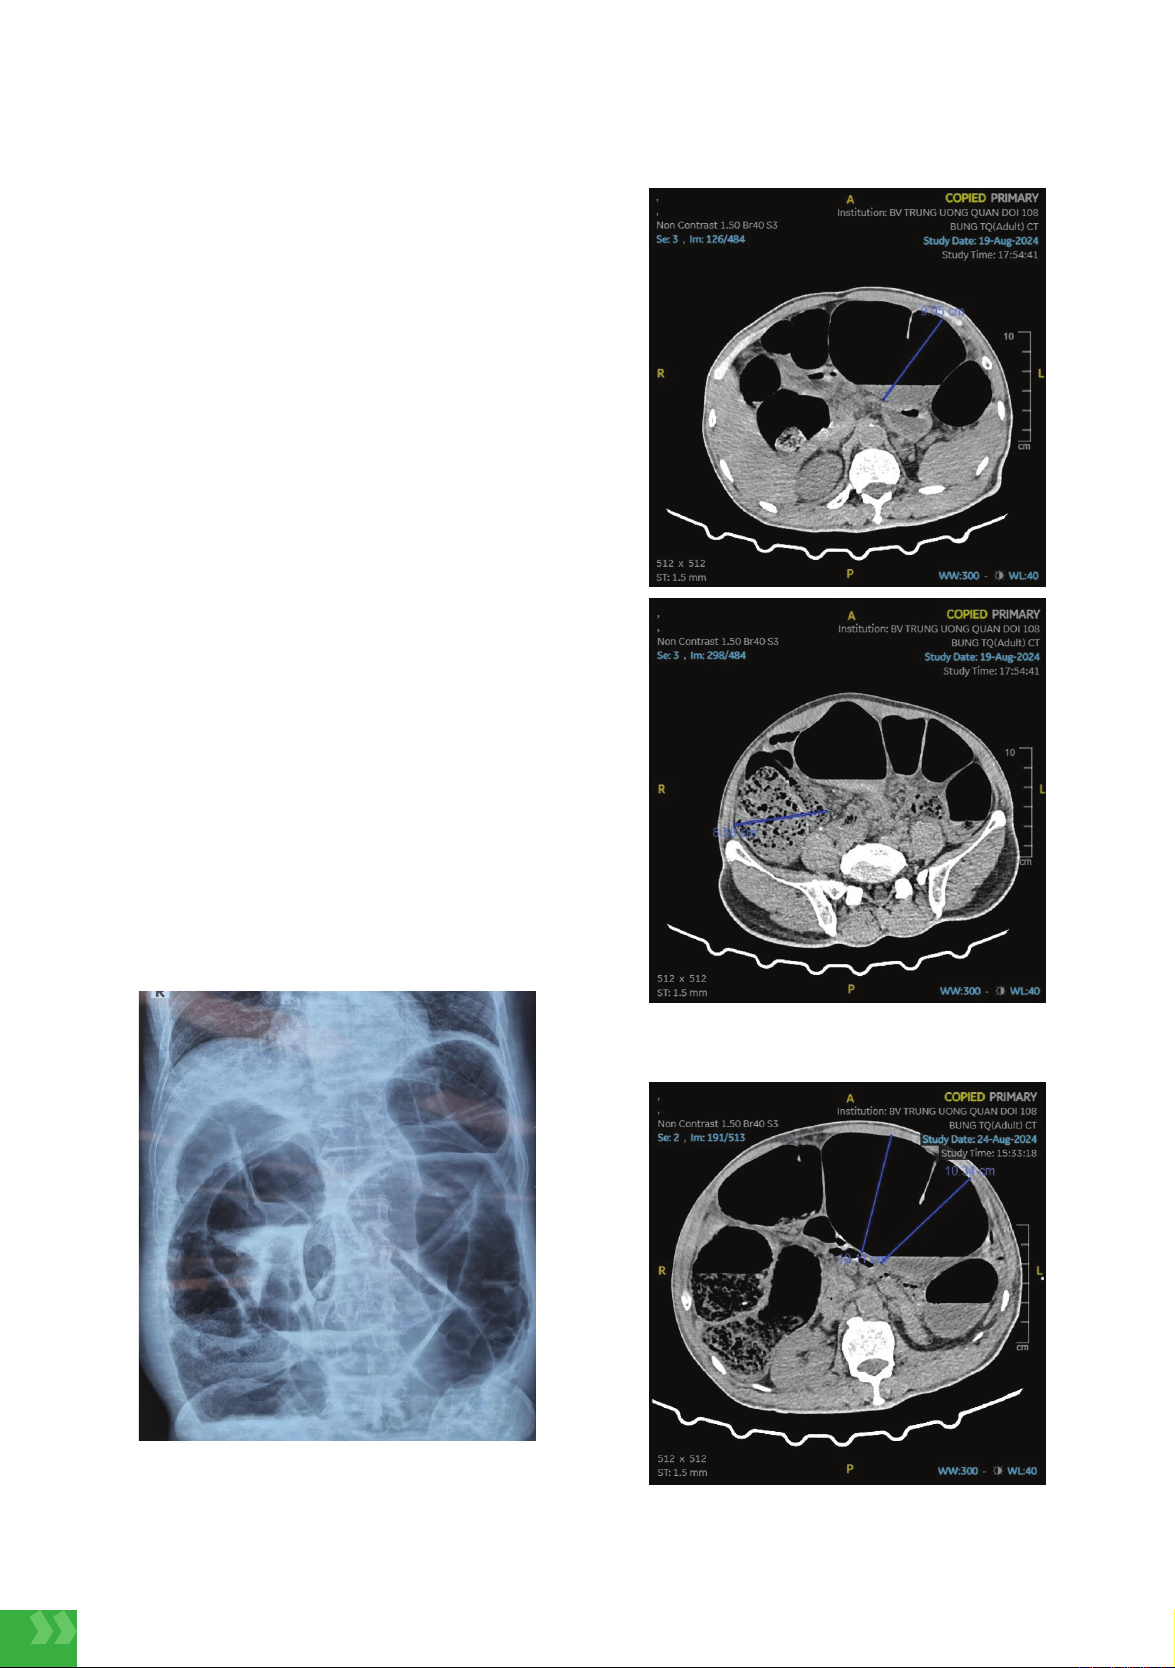

Chụp X quang bụng không chuẩn bị thấy hình ảnh

giãn lớn quai đại tràng, theo dõi tắc ruột thấp (hình

1). Chụp cắt lớp vi tính bụng thấy hình ảnh giãn lớn

toàn bộ khung đại tràng, hình ảnh tắc ruột thấp nghi

do xoắn (hình 2). Bệnh nhân đã được phẫu thuật

Hình 1. Hình ảnh chụp X quang bụng

không chuẩn bị

Hình 2. Hình ảnh chụp cắt lớp vi tính ổ bụng

ngày thứ 3 của bệnh

Hình 3. Hình ảnh chụp cắt lớp vi tính ổ bụng

ngày thứ 8 của bệnh

tôi trên hình ảnh chụp cắt lớp vi tính ổ bụng vào ngày

thứ 8 của bệnh thấy giãn toàn bộ đại tràng với đường

kính là 10,34 cm, manh tràng giãn 11,3 cm.